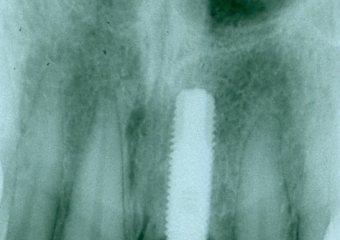

Raio X após a prótese instalada sobre implante

Raio X de 15 meses de controle

Raio X de 03 anos e 08 meses de controle